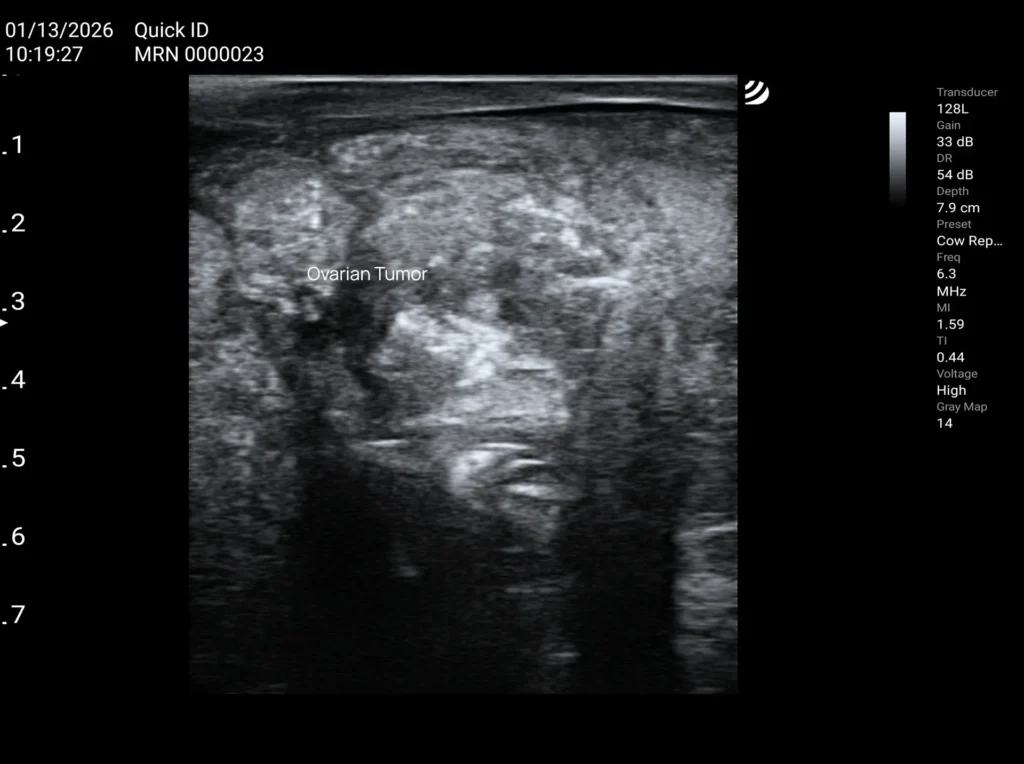

Tumor de células de la granulosa ovárica

Se detecta con mayor frecuencia durante un examen rectal, generalmente solo una vez que ha alcanzado un tamaño considerable y provoca una deformación notable del ovario.